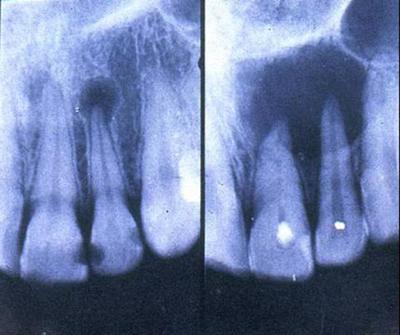

牙槽膿腫是不可忽視的一個(ge) 常見疾 ,它還有另外一個(ge) 名字叫做根尖周膿腫,常見的症狀是劇烈的疼痛,實際上是根尖周 變沒有及時治療,導致 情繼續惡化發展化膿,成為(wei) 牙槽膿腫,那麽(me) 牙槽膿腫怎麽(me) 治療?...

深圳牙科醫院醫生表示,牙槽膿腫的主要症狀和牙根尖周的症狀相似,主要症狀是劇烈疼痛,所以需要及時治療。一般治療前需要通過口腔檢查來確診是否為(wei) 牙槽膿腫,如果是一般需要及時治療,主要是排膿,讓膿液和壞死物質快速排出,減輕疼痛。

2、開髓引流:直接開髓,建立根尖引流通道也可以舒緩壓力,等到症狀緩解後及時做根管治療。